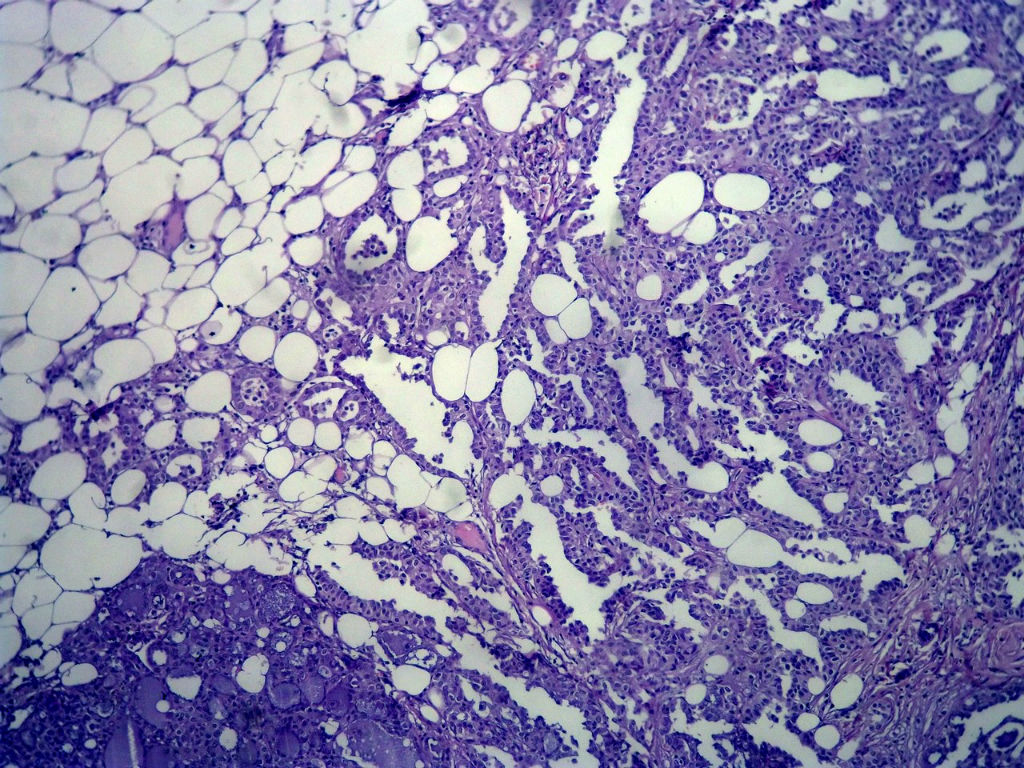

今天的一例术中冰冻。女,49岁,乳腺肿块。人气不旺,换个标题

腺病?癌?其他?(12楼常规,24楼免疫组化及会诊结果)图1

标签:浸润性导管癌 分泌癌 硬化性腺病

1. Most likely no invasive cancer

2 Sclerosing adenosis

3 Ductal epithelial hyperplasia

4. Bundles d Smooth muscle?

导管是乎可见双层上皮,部分上皮增生并有一定异型,考虑硬化性腺病,待石蜡。

导管可见双层上皮,部分上皮增生并有一定异型,考虑硬化性腺病

冰冻符合乳腺腺病

腺体与腺体之间的对比差异太大,不放心,不除外是癌,如果是我的病例,再次取材冰冻